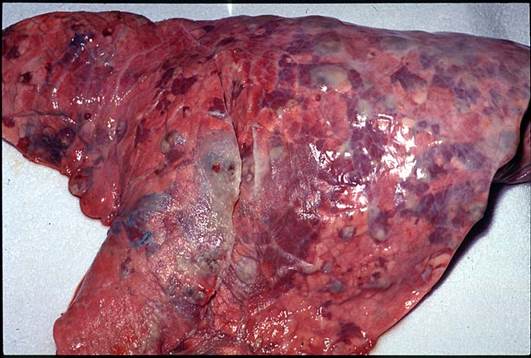

Сап — инфекционное заболевание однокопытных животных, вызывается P. mallei и характеризуется специфическим воспалением органов с образованием гранулем. Животные инфицируются возбудителем алиментарным путем, реже через конъюнктиву и слизистую оболочку носа (когда на них попадают капельки гноя, содержащие сапные микробы), и через кожу. В естественных условиях первичные поражения возникают в легких, куда сапные микробы попадают с кровью. Вокруг микробов скапливаются нейтрофильные лейкоциты, соседние альвеолы заполняются серозно-фибринозным экссудатом с лейкоцитами. Начинают размножаться мезенхимальные клетки с образованием зон эпителиоидных, лимфоидных клеток. Центральная часть очага быстро подвергается некрозу, ядра лейкоцитов распадаются на глыбки (кариорексис). В дальнейшем, некротический центр расширяется за счет распада прилегающих эпителиоидных клеток и тканей органа. Макроскопически сформировавшийся сапный узелок округлой формы, плотной консистенции. В легких сапные поражения могут быть в виде милиарных, крупноочаговых узелков и в виде сапной бронхопневмонии. Эти формы поражения сходны с туберкулезными поражениями.

Рис. 33. Легкие осла при сапе